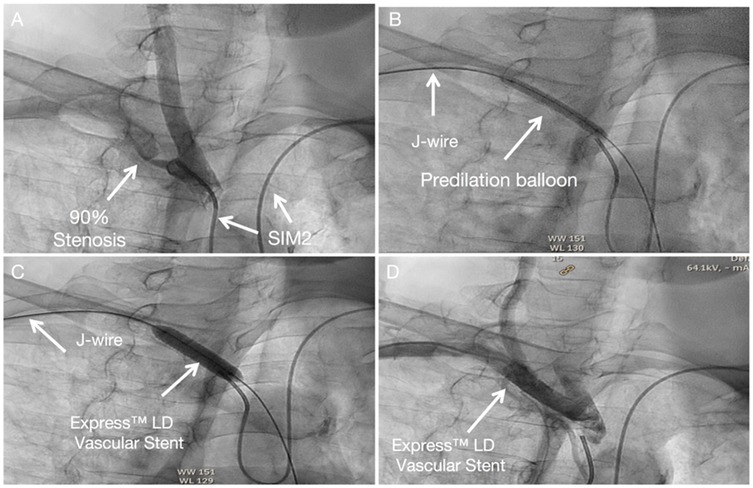

The procedural steps mirror those for left subclavian artery intervention, with transposition of the angiography and intervention access sites. Technical details are available in the Supplementary Material 3, Figure 4.

Figure 4. Subclavian stenting procedure method of right Non-CTO subclavian stenosis (A) SIM 2 catheter from left-hand access engaged in the proximal cap of left subclavian artery stenosis. (B) A predilation balloon was advanced over the J-tip wire via right-hand access and was typically inflated at low pressure. (C) An Express™ LD Vascular Stent was delivered without a guide catheter, positioned across the lesion and deployed. (D) Angiography from SIM2 showed no stenosis in stent.